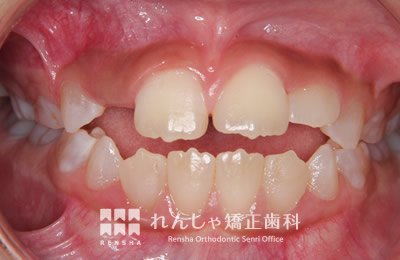

子供

混合歯列(乳歯と永久歯が歯列内に混在している時期:6~10歳頃)の場合は、歯列を大きくすることで叢生を改善できる場合があります。このケースでは取り外しできる拡大床装置を就寝時のみ約1年間、装着してもらいました。

治療前

治療中(1年6か月後)

| 主訴 | 前歯のがたつき |

|---|---|

| 診断名 | Angle Class II 叢生を伴う上顎前突 |

| 初診時年齢 | 8歳0か月 |

| 装置名 | 拡大床装置 機能的矯正装置 |

| 抜歯非抜歯 | 非抜歯 |

| 治療期間 | 1年6か月 |

| 費用の目安 | 約32万円+消費税(検査料金、都度の処置費用等も合わせた総額) |

| リスク副作用 | 歯の移動に伴う軽微な歯根吸収、歯槽骨吸収、歯肉退縮(いずれも本症例ではほぼ無し)、矯正器具装着中のカリエスリスク増大(本症例ではカリエス発生無し) |